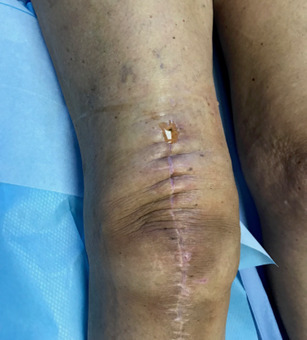

Les troubles cicatriciels sont fréquents. Un écoulement sanglant ou sérosanglant est possible pendant sept à dix jours. Sa persistance, et surtout sa survenue alors que la plaie était initialement sèche, fait évoquer une complication infectieuse (fig. 5).

Les infections, plus graves en présence de matériel, compliquent en moyenne 1 % des interventions en orthopédie. Leur taux de guérison est variable selon la situation clinique, l’état général du patient, le délai et les modalités de leur prise en charge.

Même pour un chirurgien entraîné, différencier un accident cicatriciel à traiter par soins locaux et une infection à son ­début peut être difficile.

Constater un accident cicatriciel doit faire demander en urgence un avis chirurgical, physique ou distanciel et faire prescrire un bilan biologique (hémogramme, CRP). Si une surveillance est décidée, fréquence et type de pansements sont modifiés.

Toute altération cicatricielle au-delà d’un mois après la chirurgie évoque une complication infectieuse, qui est certaine en cas de fistule sur – ou à proximité – de la cicatrice (fig. 6).